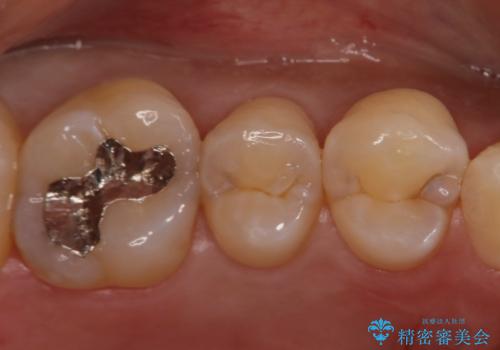

- 歯によく繊維質なものがはさまることが気になり来院されました。レントゲン等から隣接カリエス(歯間にできるう蝕)があることが分かり、清掃性が高く、審美的なセラミックインレーで治療を行いました。